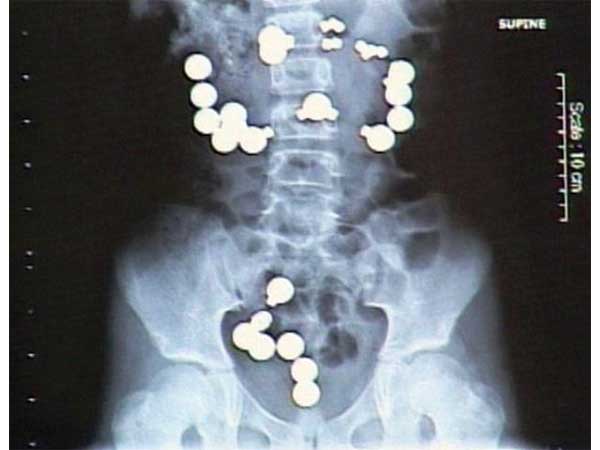

Drugs

A Nigerian man was caught at an airport in Malaysia while he was trying to export 52 capsules of methamphetamine. Wonder how would he get all these capsules out of his body! Phew.